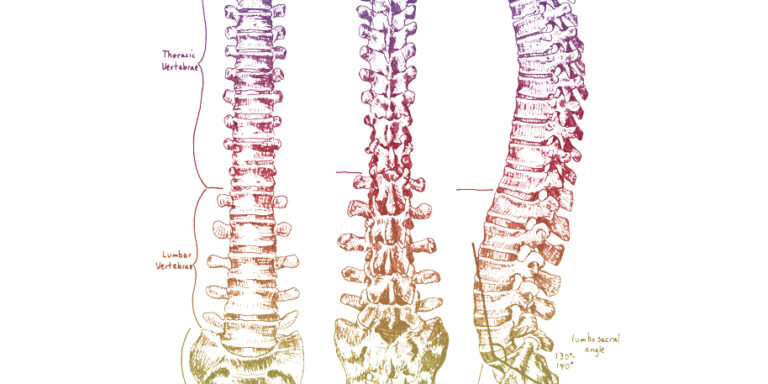

The parasympathetic nervous system, the sympathetic nervous system, and the enteric nervous system comprise the autonomic nervous system in the body. The autonomic nervous system is continuously active and is responsible for unconscious regulation of our glands and organs. The parasympathetic nervous system takes care of “rest and repair” activities, such as salivation, tears, sexual…